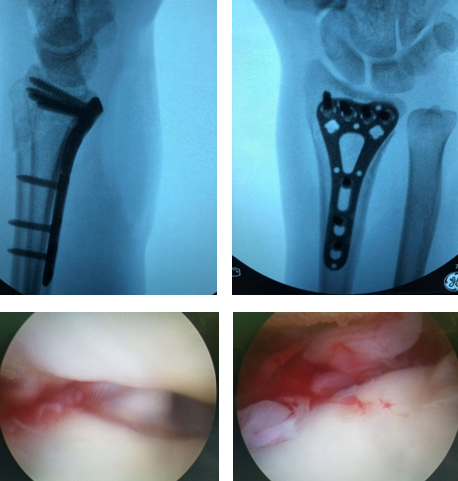

过了两天,齐主任手术团队为女士进行了手术,采用“关节镜下的植骨内固定术”。齐主任帮她用钢板内固定,手术顺利,术后恢复情况不错,齐主任叮嘱了她一些注意事项,她就出院了。

半年后,女士来找齐主任复查,她满面红光地对齐主任说:“齐主任,我对您佩服得五体投地!您瞧瞧我这左手,跟右手没啥区别!”齐主任让她做一些伸、握、対掌、旋转的动作,她都很灵活,负重也是可以的。